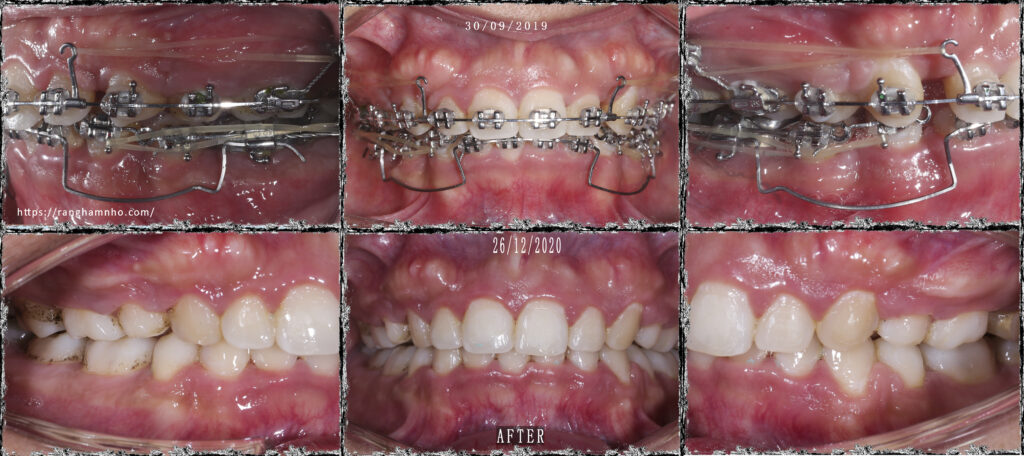

iBệnh nhân này đã được điều trị 2 năm tại một cơ sở phòng khám nha khoa khác. Bệnh nhân hô cả răng và xương & cười hở lợi. Tình trạng niềng hỏng rất nghiêm trọng, khớp cắn sâu 100%, mặt hô nhiều chưa được cải thiện.

Bệnh nhân được giải quyết khớp cắn sâu bằng cung tiện ích UA trên dây TMA 17×25. Kết quả không được hoàn hảo, nhưng là chấp nhận được đối với 1 case niềng hỏng đã quá thời gian điều trị rất lâu.

Hiệu ứng cuộn trong chỉnh nha (Bowing effect) là tình trạng các nhóm răng không dịch chuyển tịnh tiến theo mong muốn mà khi đó, các nhóm răng trước và nhóm răng sau bị “cuộn” lên gây hở khớp ở nhóm răng hàm nhỏ, nhiều trường hợp nặng gây hở cả khớp ở răng 6. Khi đó, các răng cửa và răng hàm đều trồi cao.

Có nhiều nguyên nhân gây hiệu ứng cuộn: lực kéo đóng khoảng quá mạnh, lực kéo đóng khoảng quá xa tâm cản, đường cong spee trước điều trị quá sâu, gắn sai mắc cài……..